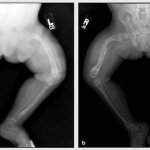

Warts on the soles appear as hard, round lumps with papillae in the middle. Inside the wart, characteristic black dots are visible - many small thrombosed capillaries. Along the edges there is a small roll of keratinized skin. The visible part, rising above the surface of the skin by only 1-2 mm, can reach 2 cm in diameter and is only a quarter of the total size of the plantar wart, which mainly forms in the deep layers of the epithelium (skin).

Externally, the spine resembles a callus. A plantar wart can be differentiated (distinguished) from a callus by the visible interruption of the skin pattern in accordance with the wart.

Plantar warts themselves do not pose a threat to health, but when walking they cause a person significant discomfort, cause pain, which often intensifies, and can even bleed. This is due to the location of the tumor and the specifics of its growth. Since the spine grows inward, the weight of the body when walking compresses the pain receptors.